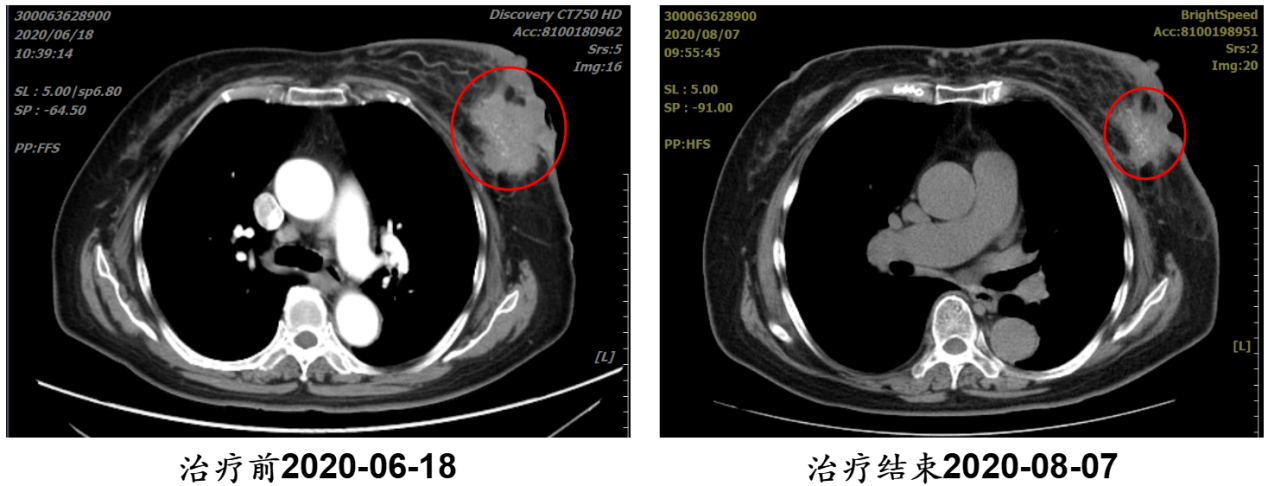

病例1:81岁乳腺癌晚期,胸壁破溃,3个月愈合

· 诊断:左侧乳腺癌浸润性癌,cT4N3M1 Ⅳ期(胸壁皮肤侵犯、破溃)

· 难治点:高龄、晚期、无法手术,常规放疗恐加重皮肤损伤

· 重(碳)离子治疗:2020年7—8月完成疗程

· 结果:治疗后3个月,肿瘤显著缩小,皮肤破溃处完全愈合,疼痛消失

点评:对重(碳)离子而言,年龄大、病期晚,不再是不治的理由。

【病例提供医生:杨钰铃 科室:放疗中心一科】